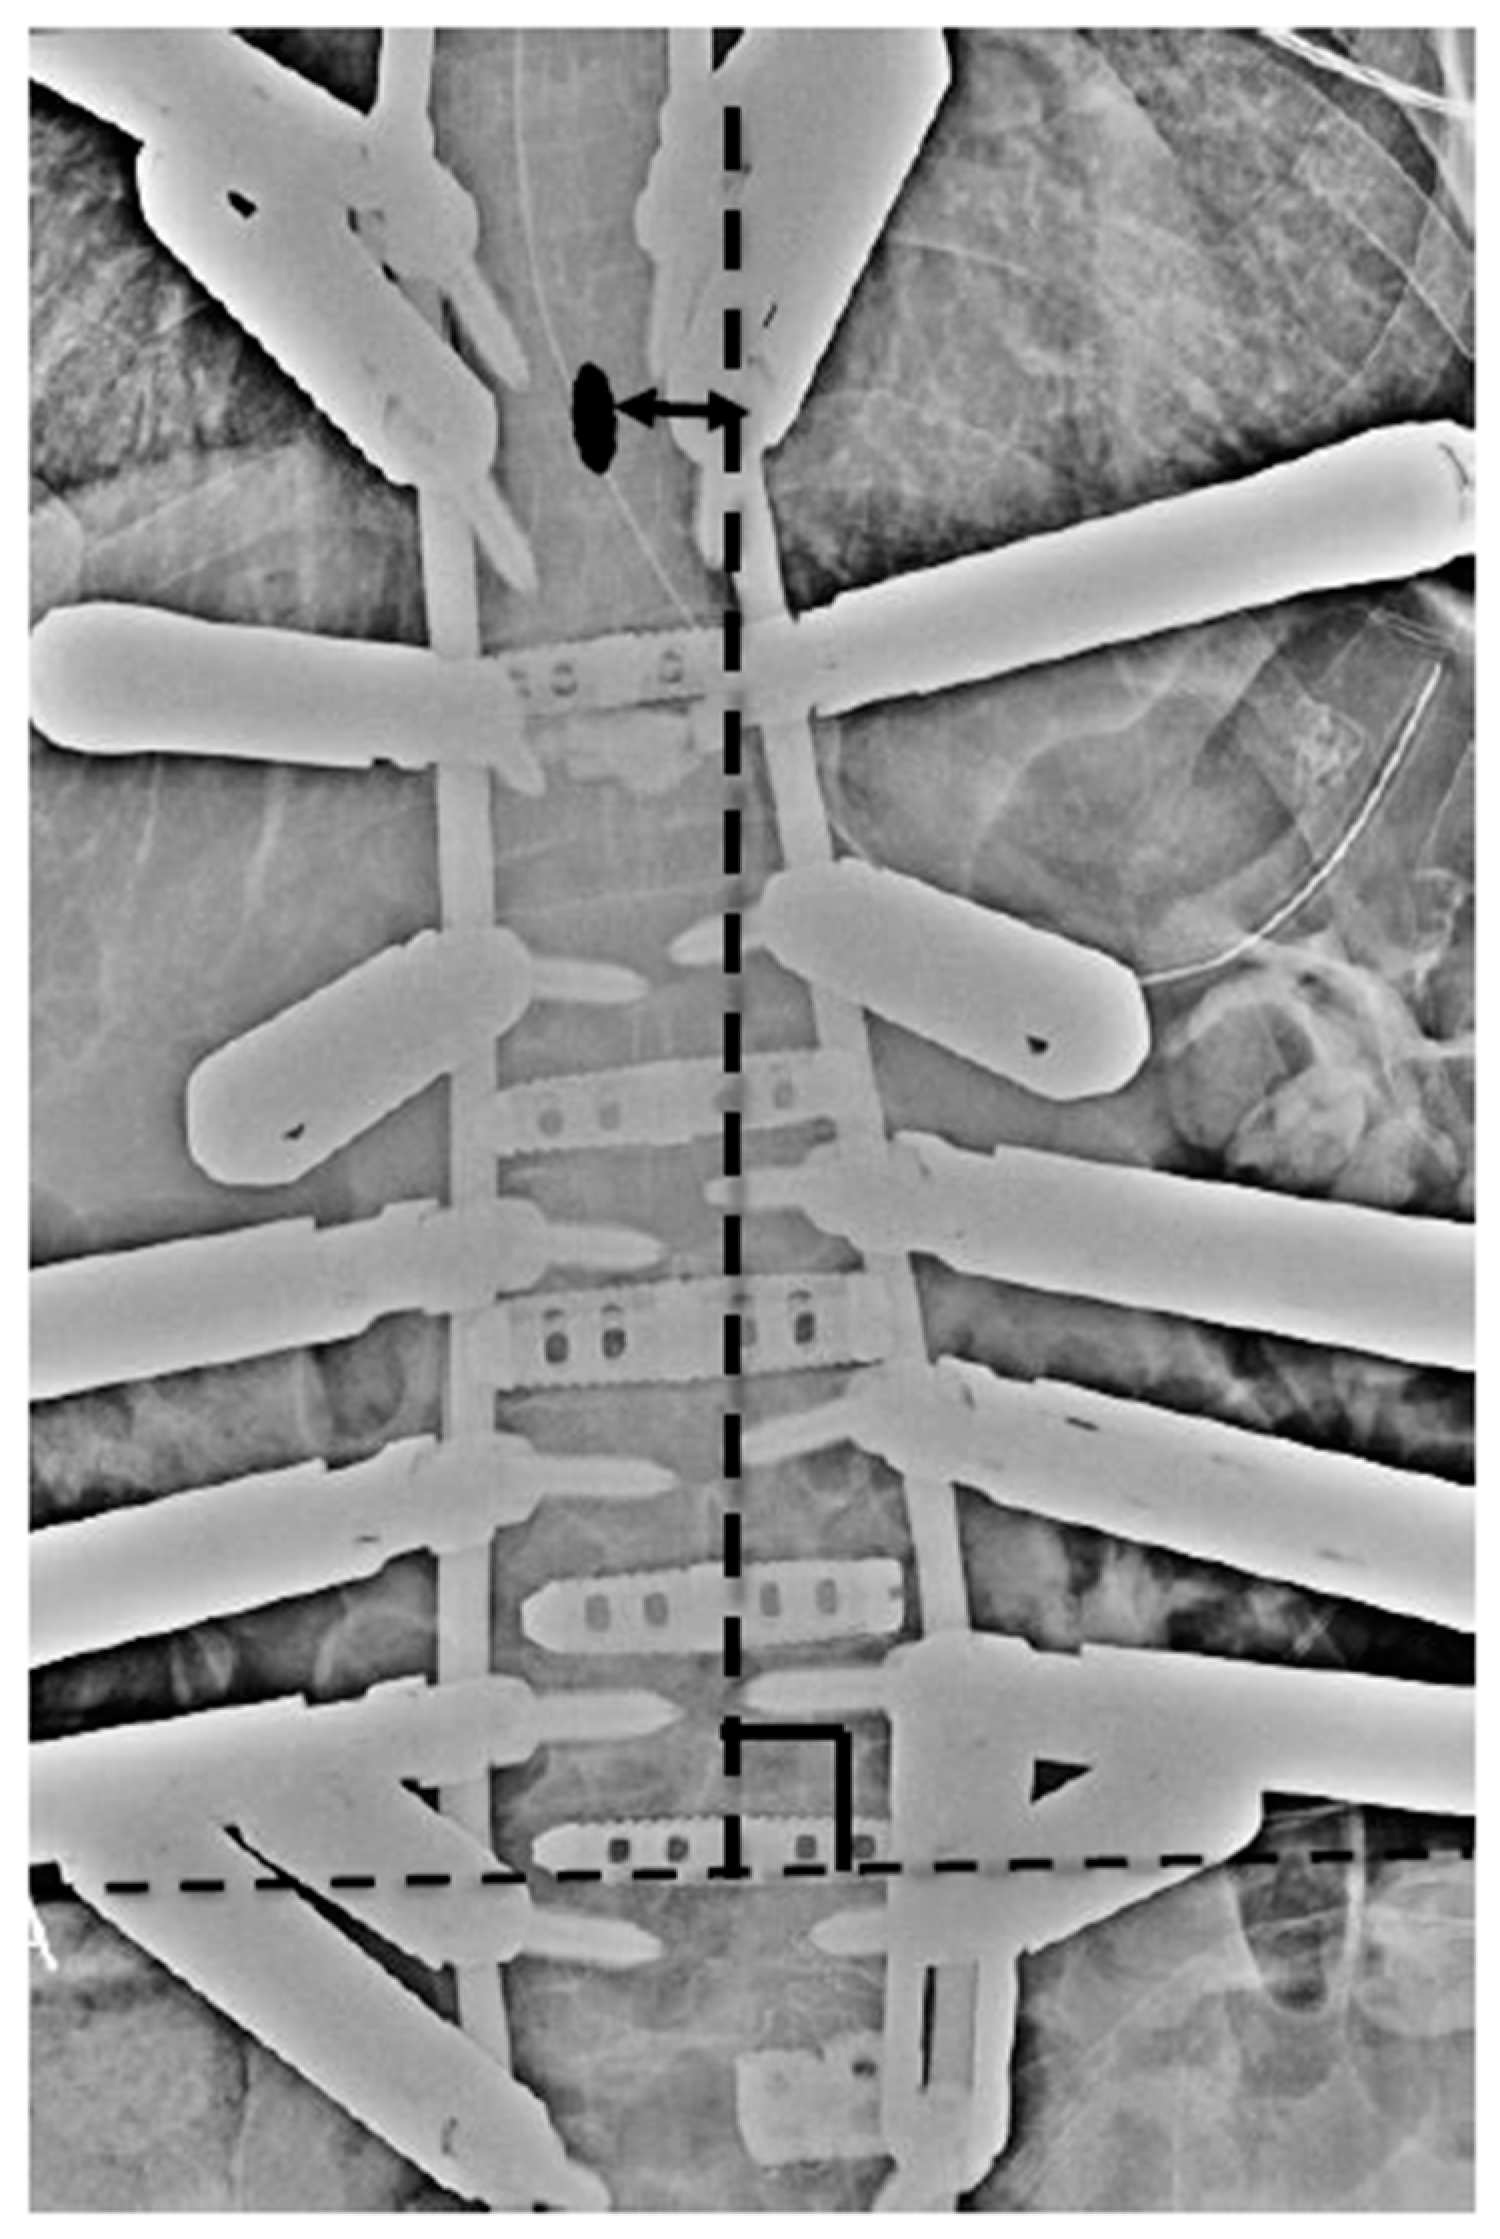

3.1. Case Study 1: RR

3.2. Case Study 2: RR and SD

3.3. Case Study 3: RR and KR